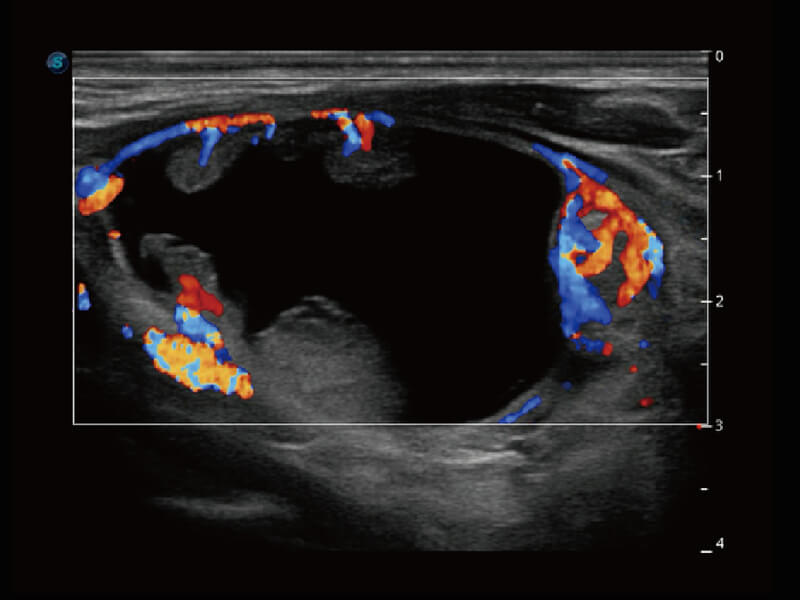

Micro F 显微血流成像 明察秋毫

临床图